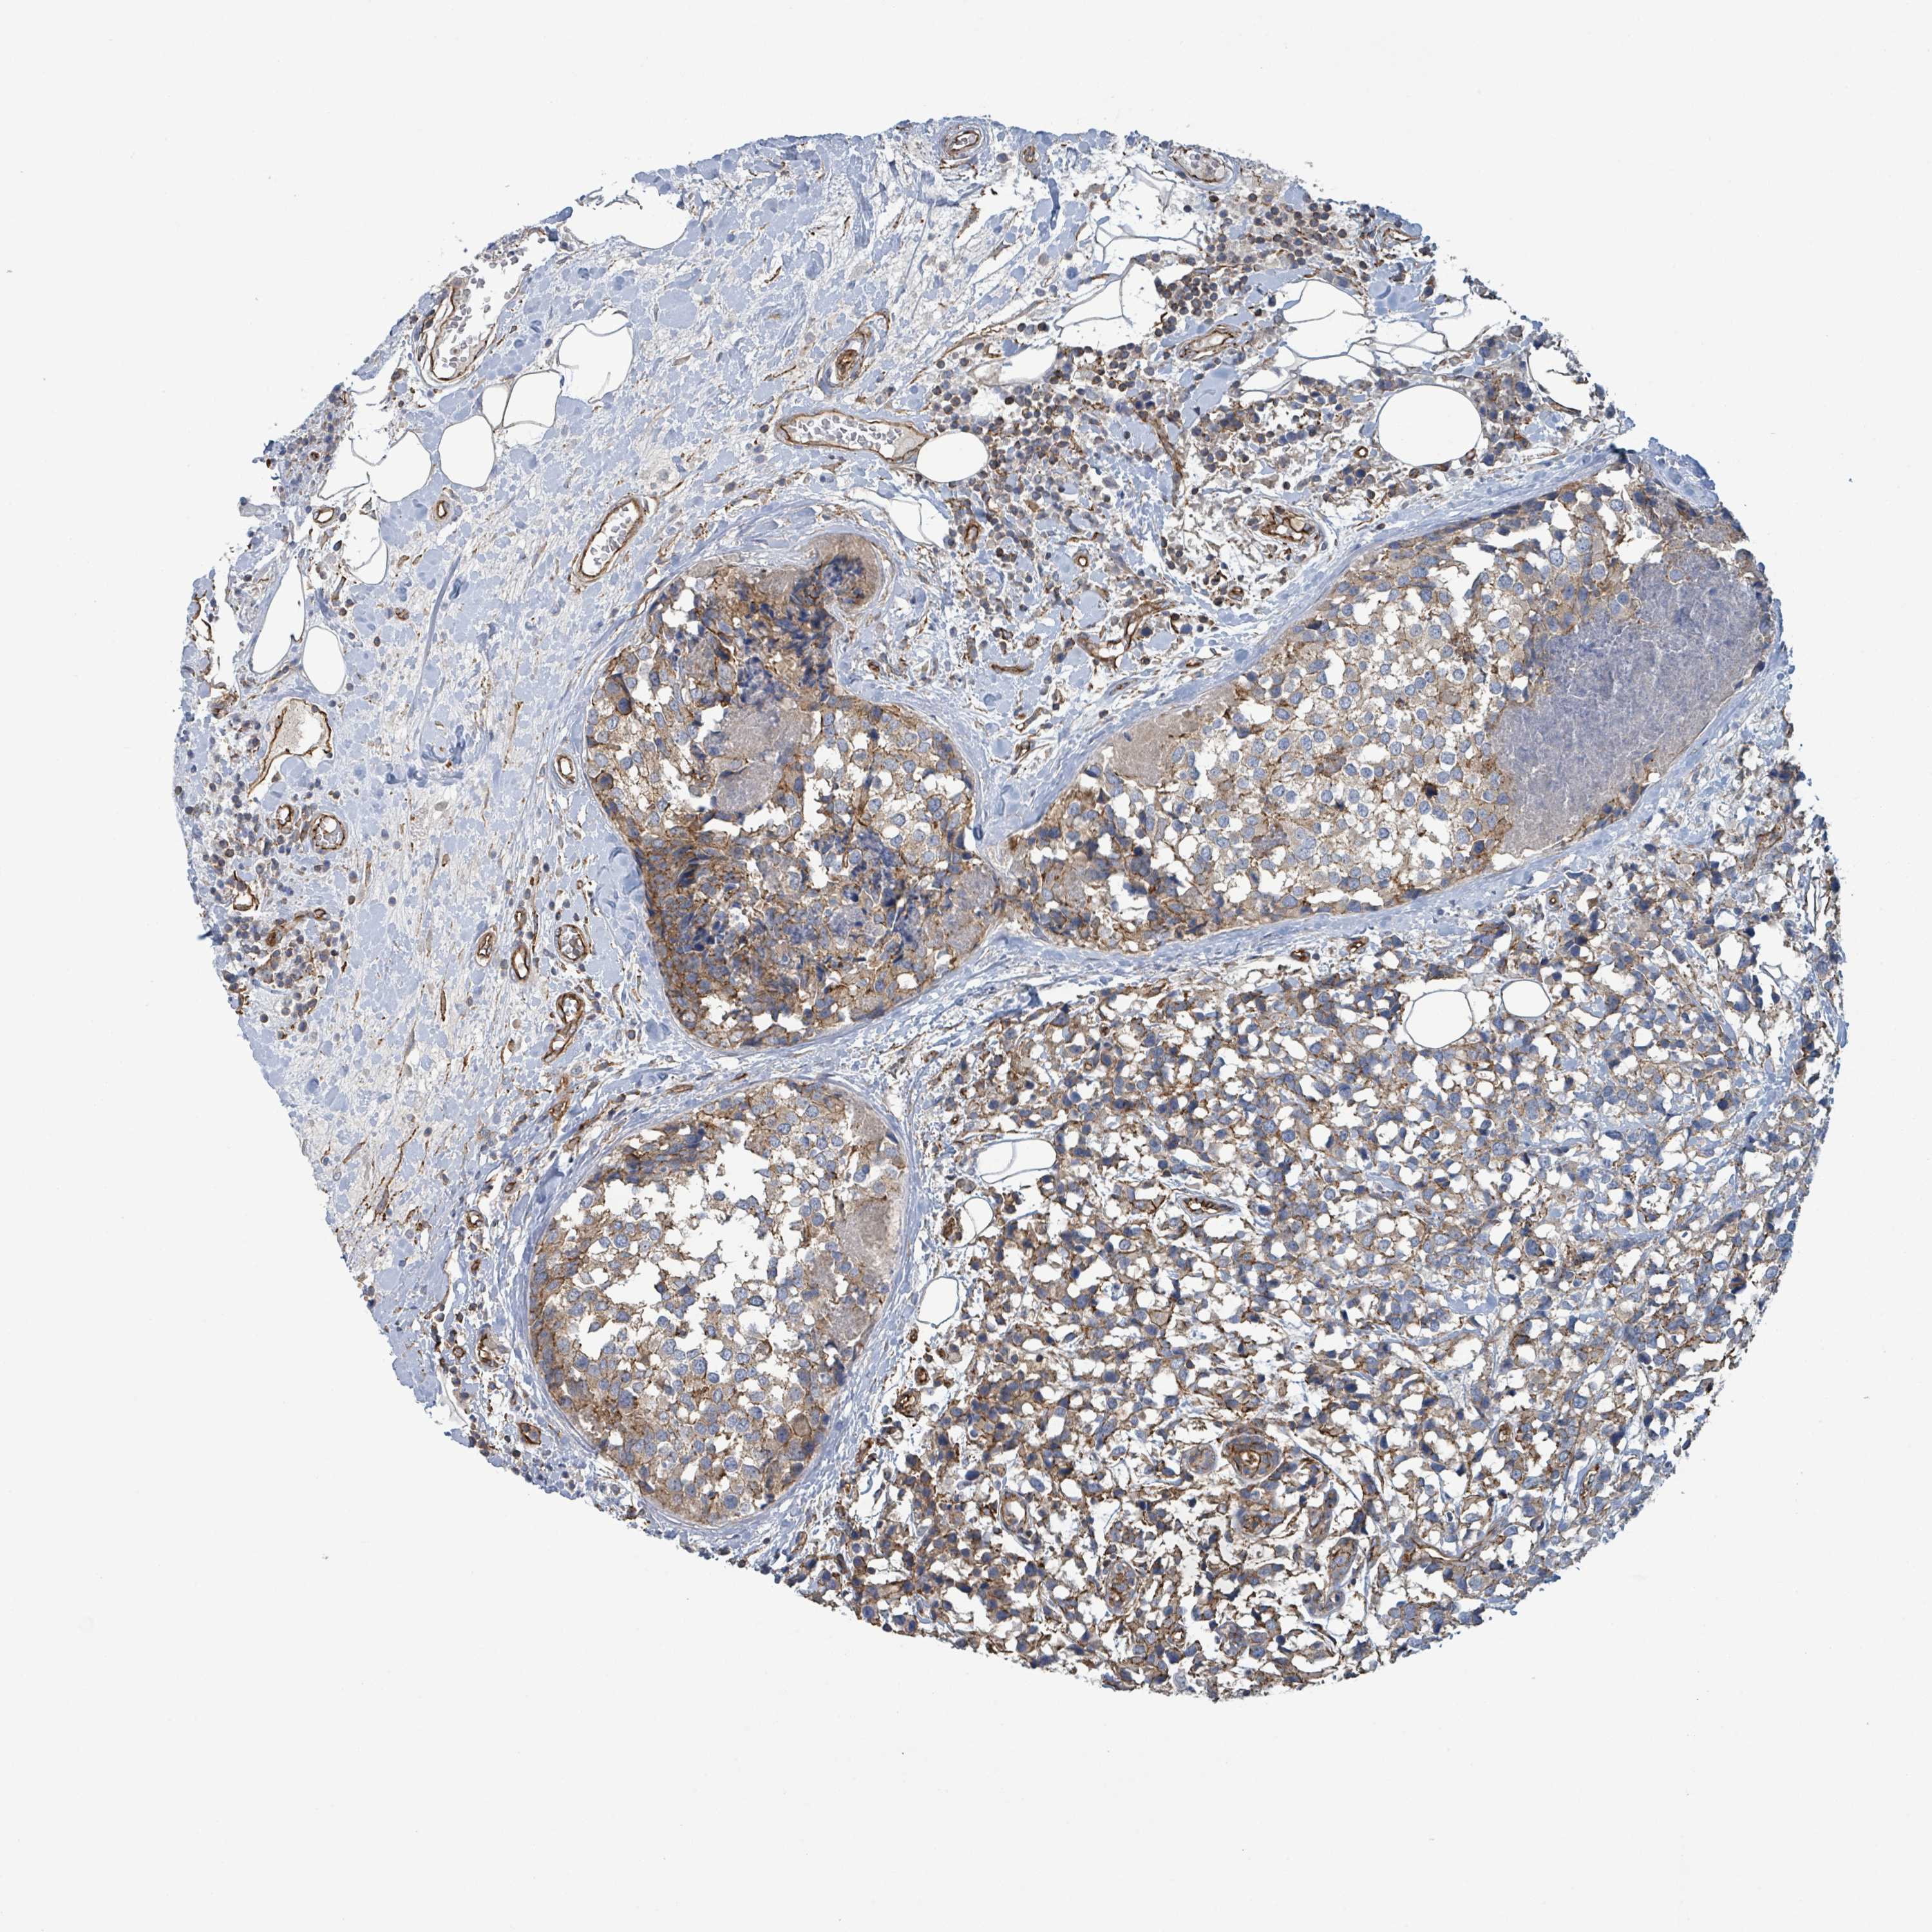

CANCER BREAST CANCER Show tissue menu

BRCA TCGA BRCA VALIDATION PROTEIN EXPRESSION